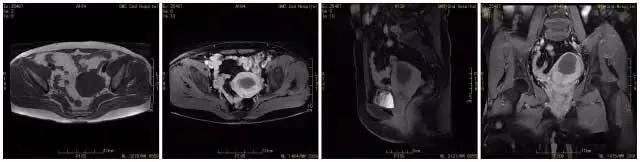

王女士 术前MRI显示子宫肌瘤大小约9cmX7cm

王女士术后MRI显示原病灶明显坏死、缩小,大小约5cmX4cm,随着时间的延长病灶将进一步缩小。